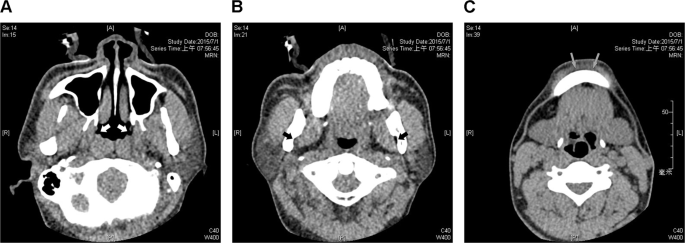

Three lateral wall levels (nasopharynx, oropharynx, and subglosso-supraglottis) were further defined by radiographic landmarks that could be easily recognized in axial CT images. The nasopharyngeal level was defined as where the Eustachian tube orifice was located (Fig. 1A). The oropharyngeal level was defined as where the mandibular foramen was located (Fig. 1B), and the subglosso-supraglottic level was defined as where the mental tubercle was located (Fig. 1C).

Radiographic landmarks of three representative parapharyngeal fat pad areas in axial images. The nasopharyngeal level of parapharyngeal fat pad was defined as where the Eustachian tube orifices (white arrows) are located (A). The oropharyngeal level was defined as where the mandibular foramens (black arrows) are located (B). The subglosso-supraglottic level was defined as where the mental tubercles (grey arrows) are located (C).